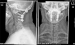

Abbildung 7: Rheumatische Wirbelsäule Röntgenaufnahmen im anterior-posterioren und seitlichen Strahlengang nach dorsaler Verschraubung von HWK 1 mit 2 durch Schrauben-Stab-System und Beckenkammspaninterposition mit Titan-Kabelcerclage gesichert. |

Röntgenaufnahmen im anterior-posterioren und seitlichen Strahlengang nach dorsaler Verschraubung von HWK 1 mit 2 durch Schrauben-Stab-System und Beckenkammspaninterposition mit Titan-Kabelcerclage gesichert. |